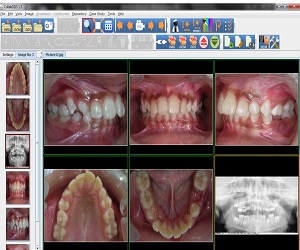

The first version of the CollabDDS V1.0 was released on July 04, 2012. Based on the continuous feedback from the experts, latest version 1.6 was released on August 19, 2014. Dental module for Cephalometric analysis has also been introduced in this version.

With the proof of concept having gone through successfully, a Pilot Project for Implementation of CollabDDS at Medical and Dental Colleges and Hospitals has been undertaken. This is an extension of the POC to the Operational Research Phase as a prelim to rollout. This pilot implementation is used to evaluate the efficiency and effectiveness of remote diagnosis. Further this phase also incorporates a module which carries out Cephalometric analysis for orthodontic surgeons to enable diagnosis and treatment planning of their patients. This phase would also include the Enhancement of CollabDDS and Advanced Applications on 3D imaging. It would involve the reconstruction of 3-D models from CT / Surface images, development of methodologies for orthopedic implant development using 3D models.